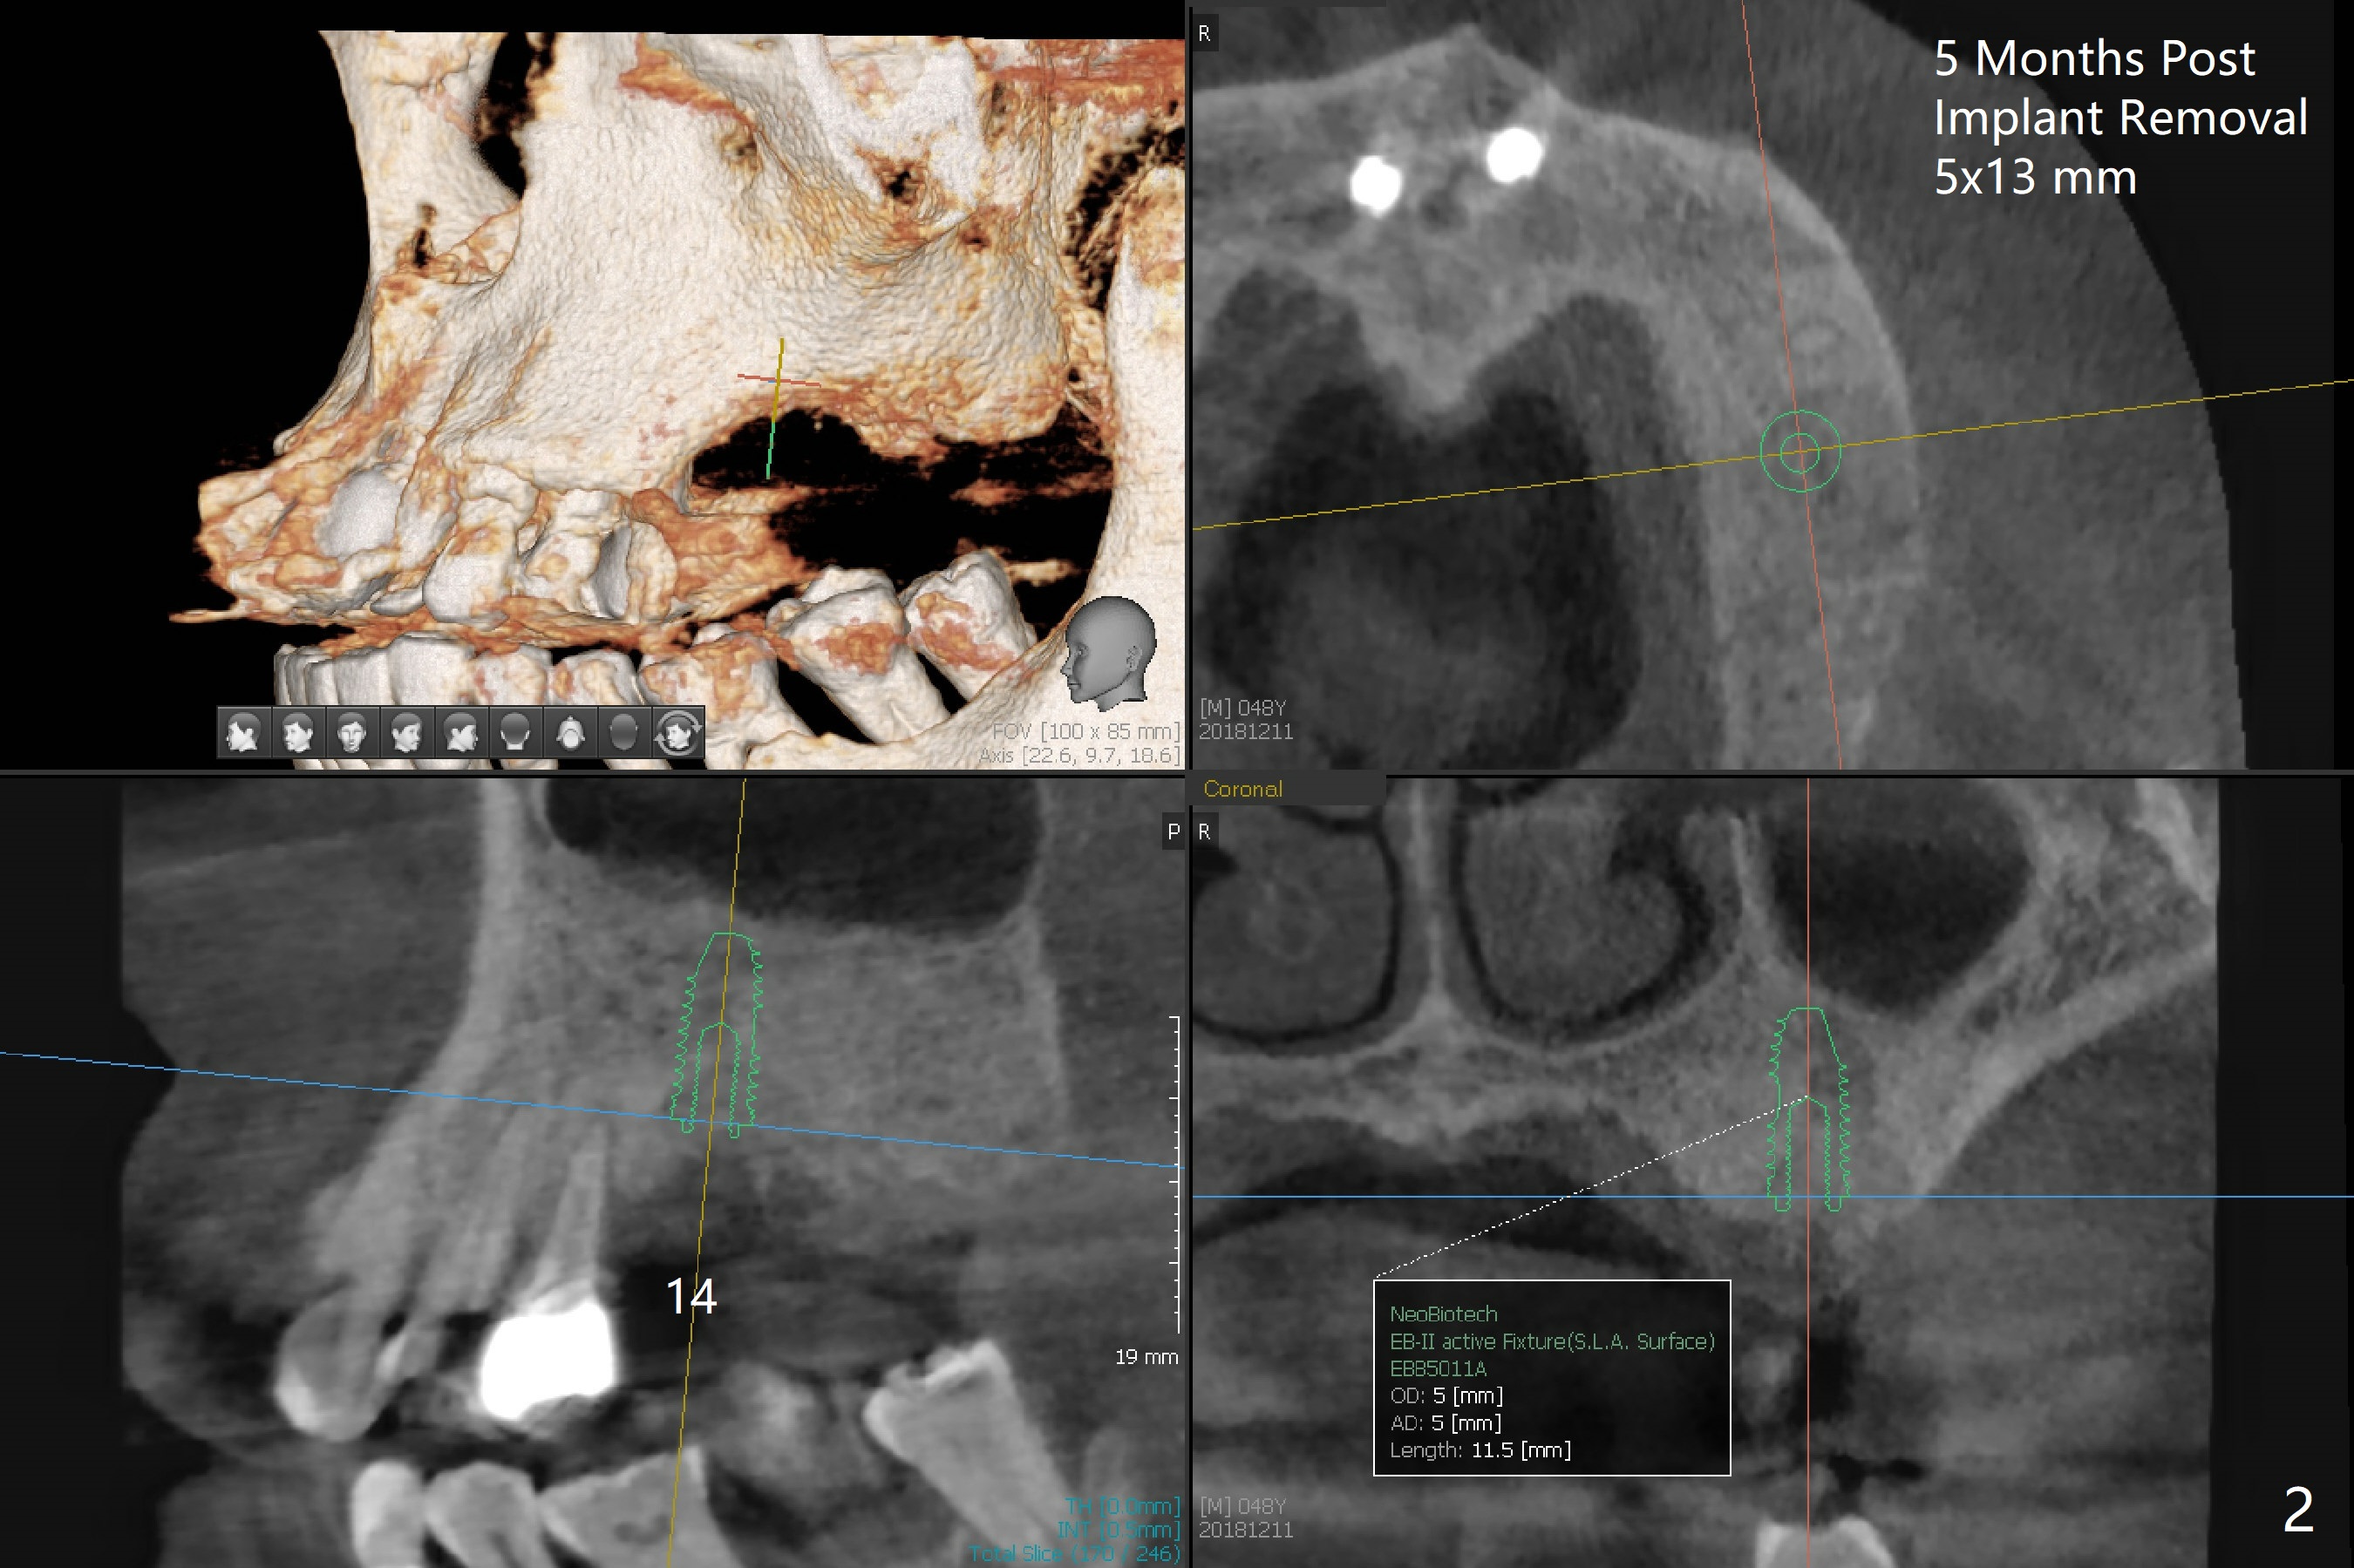

A 48-year-old man returns for implant placement at #14,15 and 29 (5 months post implant removal, 1 year post extraction and 2.5 months post implant removal, respectively, all with bone graft, Fig.1). Since the bone height at #14 and 15 is sufficient and sockets heal, implant placement will be done first (Fig.2,3), as compared to those at #29 (Fig.4). The tooth #18 is periodontally compromised with buccally cross bite (Fig.1); the position of the implant at #15 will be set up normally. When the site of #29 is ready for implant, use a large one (4.5 or 5x8.5 mm; use a dummy one as a tap).